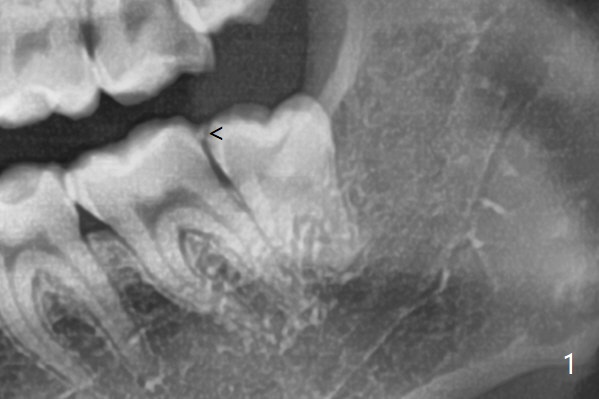

Distoangular      Last     Next